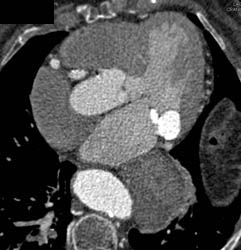

Aberrant RCA Off the Left Cusp